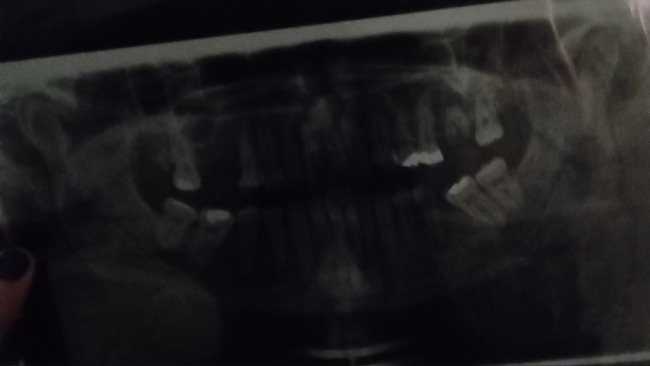

Na dzień dzisiejszy mam bardzo dużo zmian (praktycznie w każdym) zębie. Są to torbiele i zmiany naciekające.

Nie mając jeszcze 25-ciu lat muszę usunąć wszystkie zęby. Na NFZ terminy są bardzo odległe (rok to minimum) a więc muszę ogarnąć to prywatnie, tymbardziej że czas gra tu najważniejszą rolę.

Plan jest taki, aby usunąć wszystkie na raz zęby pod narkozą (1000zl narkoza+ od 250zl za usunięcia 1 zęba).